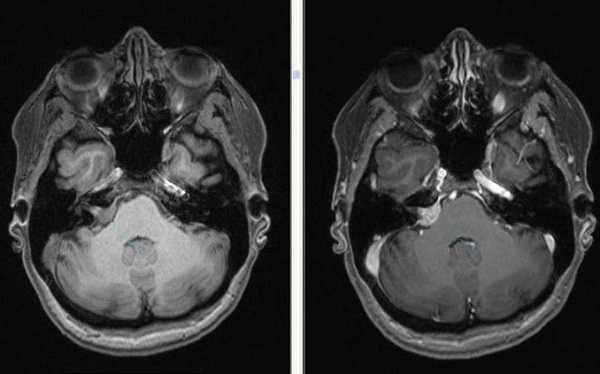

- Внутренний слуховой проход и мостомозжечковый угол - шваннома 8 нерва, менингиома височной кости, эпидермоидные (холестеатомы) и арахноидальные кисты, редко - гломусная тимпаническая опухоль.

Вестибулокохлеарный нерв (VIII) состоит из 4 пучков. Опухоли происходят обычно из вестибулярной его части. Шваннома - инкапсулированная доброкачественная (градация 1) опухоль, происходящая из дифференцированных неопластических шванновских клеток оболочек периферических нервов. Невриномы ММУ составляют около 3% опухолей головного мозга. Часть шванном (двухсторонние слуховых нервов) связана с НФ 2 типа. Пик частоты между 40 и 60 годами. Растут медленно и крайне редко малигнизируются. Клинические проявления связаны с нарушением функции нерва и компрессией ствола. Шваннома может происходить из любого отрезка по ходу нерва и хорошо прослеживается при МРТ области ММУ. Невринома видна как на Т2-взвешенных, так и на Т1-взвешенных МРТ в виде округлого образования. Невриномы хорошо и равномерно усиливаются после МРТ с введением контрастного вещества. Невриномы области цистерны могут иметь компонент во внутреннем слуховом проходе, особенно, хорошо видимый при МРТ головного мозга с контрастированием. Изредка встречаются невриномы полностью расположенные внутри канальца. Они составляют наибольшую диагностическую сложность при МРТ, требуют тонких срезов и контрастирования. Менингиомы ММУ обычно типично расположены и при МРТ имеют характерную форму и типичные черты при МРТ с контрастированием. Однако редко встречаются внутриканальцевые менингиомы. При МРТ они неотличимы от неврином. Холестеатомы при МРТ имеют смешанную интенсивность сигнала, в зависимости от их содержимого. На диффузионно-взвешенных МРТ холестеатомы обычно яркие.

Невринома ММУ на снимках МРТ (нативная и контрастная процедуры)

Перед оперативным вмешательством метод дает возможность уточнить локализацию и размеры патологического участка, в период восстановления помогает своевременно диагностировать осложнения.